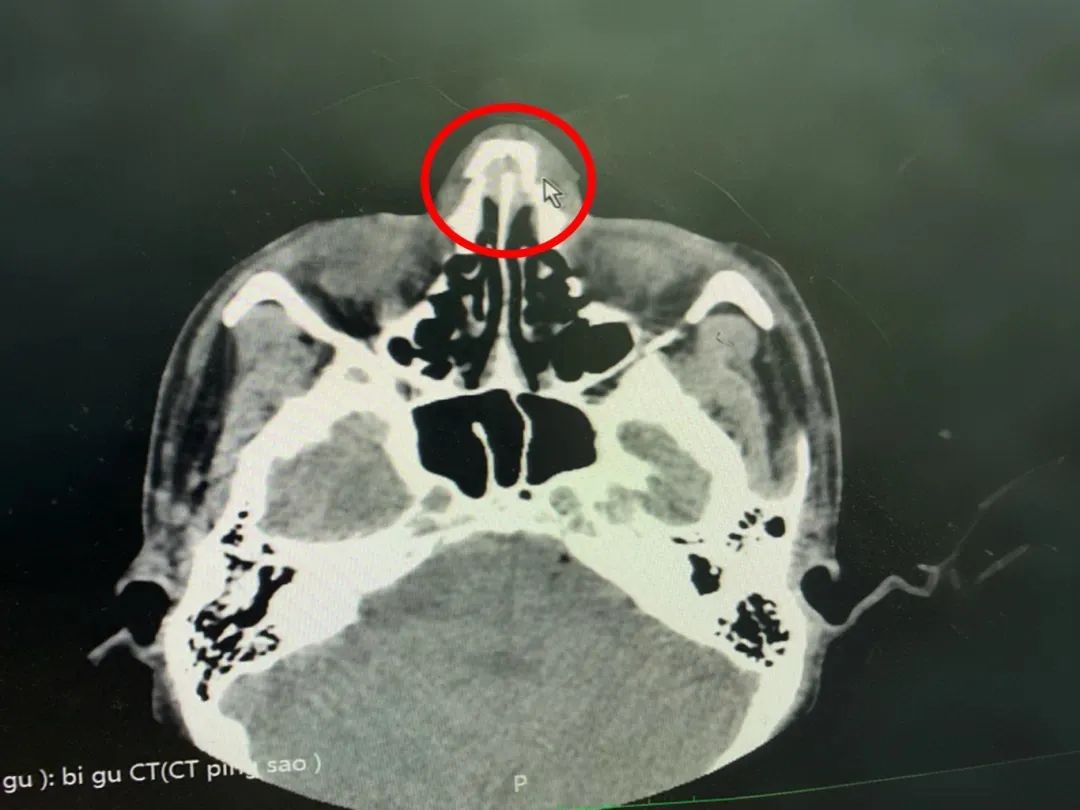

醫(yī)生通過CT檢查顯示:雙側(cè)鼻骨骨折,斷端錯位,周圍軟組織稍腫脹,正如醫(yī)生猜測的那樣,確診:“鼻骨骨折”。